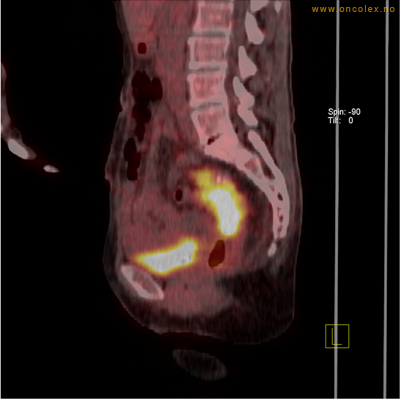

Vev som tar opp mer radioaktivt stoff, synes som hvite områder som lyser opp mer i forhold til annet vev som tar opp mindre sukker.

Høyt opptak av 18F-FDG i adenokarsinom i rektosigmoideumovergangen. Fysiologisk opptak i blæren.